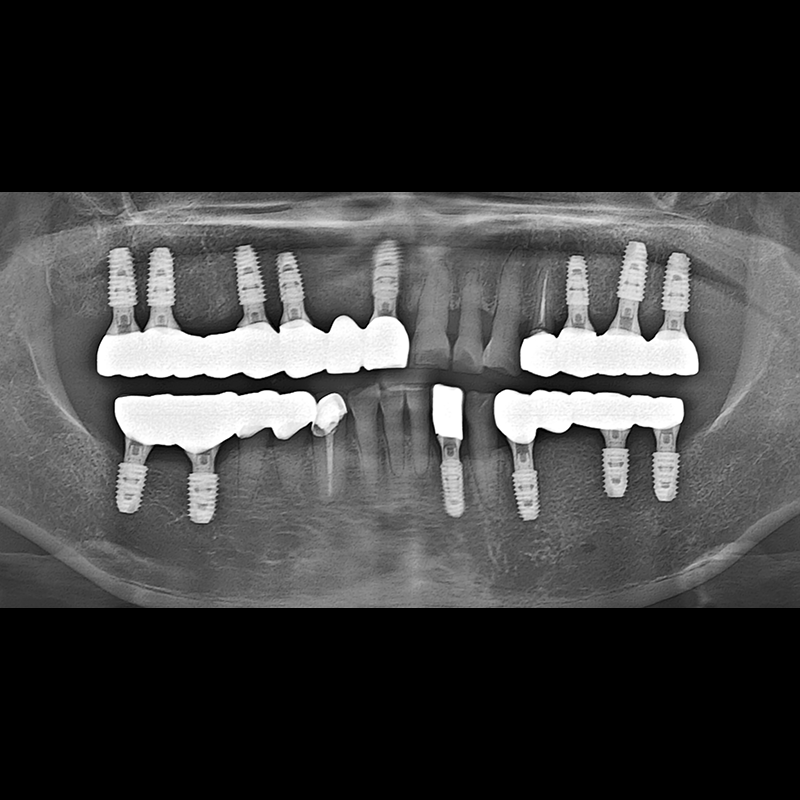

BEFORE AFTER

种植牙前后的照片 2025.05.30

在缺失的牙齿部分和难以挽救的牙齿位置植入了种植牙。